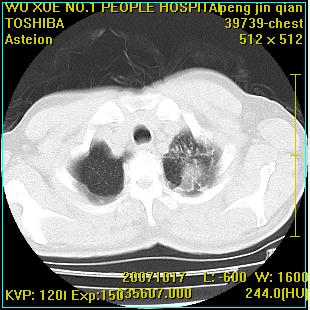

标题: CT10148:男,56岁,咳血。 [打印本页]

标题: CT10148:男,56岁,咳血。

左肺上叶尖段占位性病变,考虑肺癌.癌性空洞,并双肺转移灶及纵隔淋巴结转移

左肺上叶尖后段较大团块影,边缘光滑,内见不规则裂隙样空洞,周围明显见细小结节及渗出,与肺门方向结构紊乱,另:左上叶尖段外侧 舌叶内侧 右上叶尖段及下叶背段均见片状致密影。考虑:继发性肺结核伴空洞形成!

左上肺后壁空洞,内壁不规则,可见壁结节;左上叶尖段外侧 舌叶内侧 右上叶尖段及下叶背段均见片状致密影。考虑:左肺肺癌并两肺继发性肺结核?